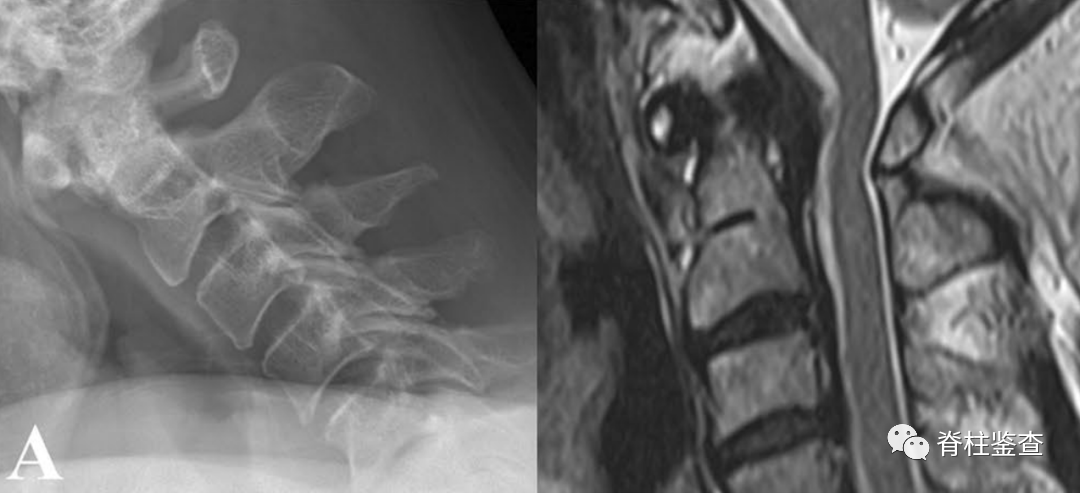

A:术前显示寰枢椎不稳定导致脊髓受压

A:术前显示寰枢椎不稳,需要行C1-C2融合